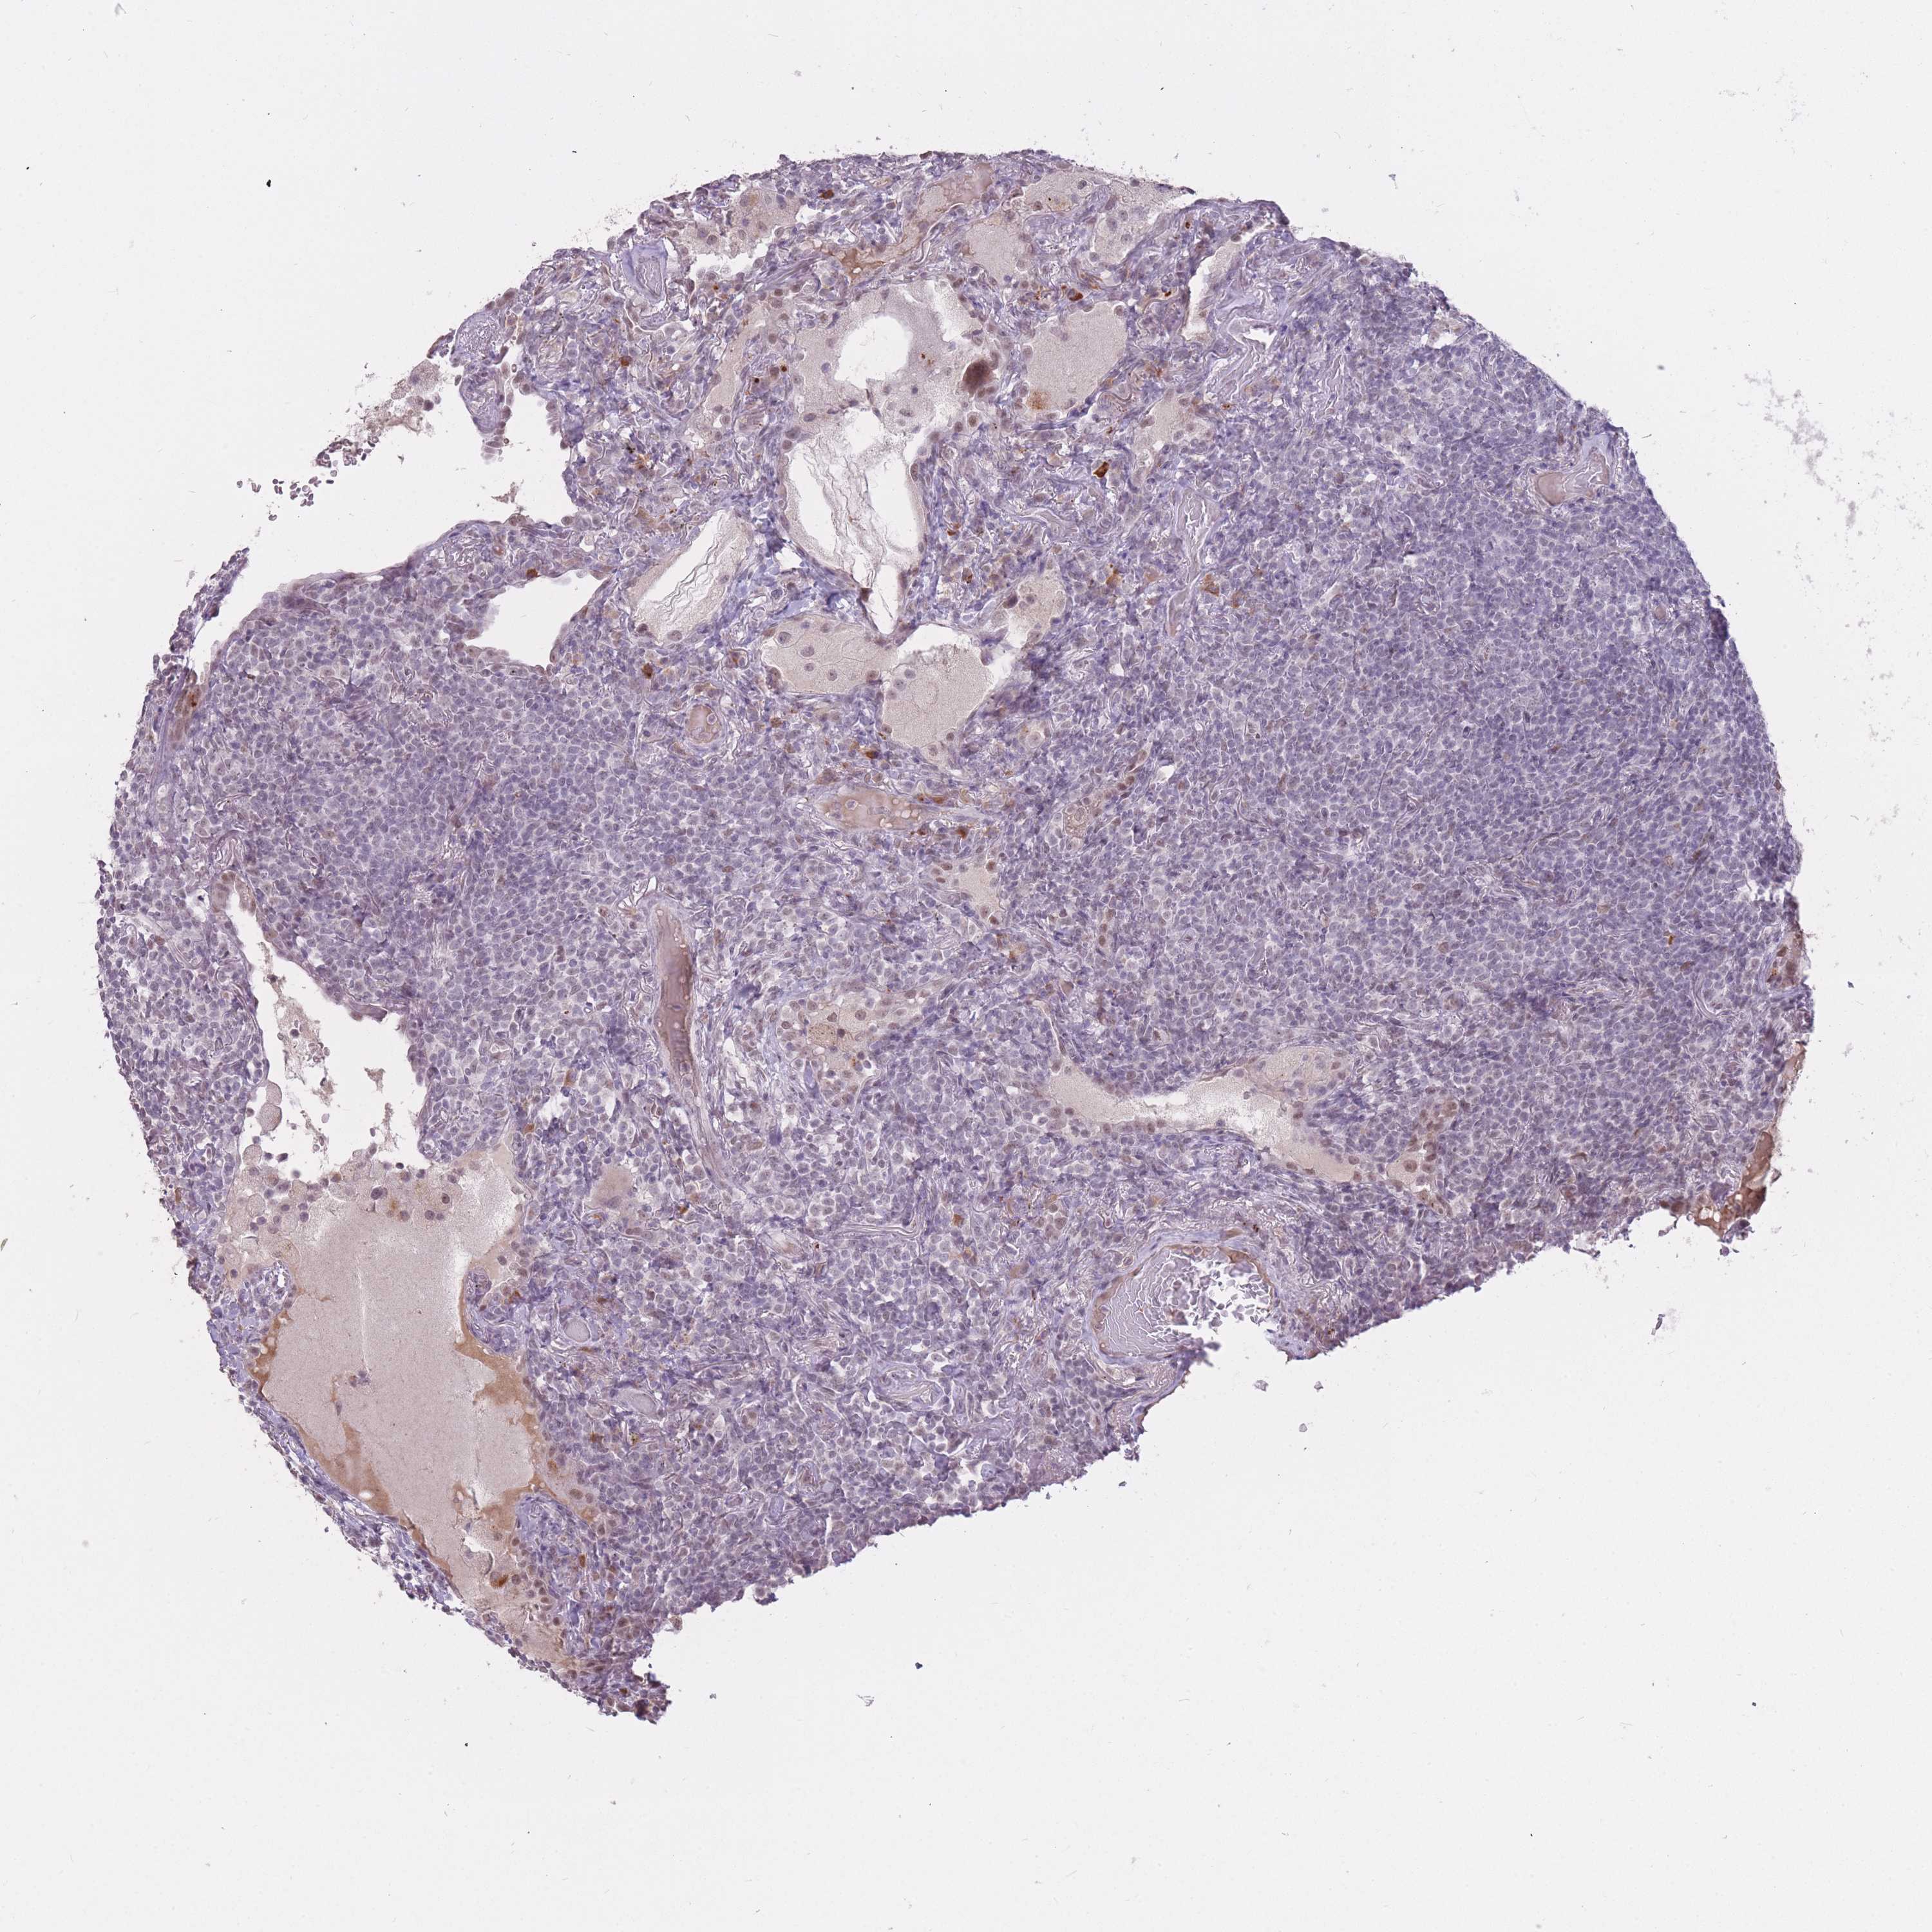

LYMPHOMA - Protein expressioni

A mouse-over function shows sample information and annotation data. Click on an image to view it in a full screen mode. Samples can be filtered based on level of antibody staining by selecting one or several of the following categories: high, medium, low and not detected. The assay and annotation is described here.

Antibody staining in the annotated cell types in the current human tissue is reported as not detected, low, medium, or high, based on conventional immunohistochemistry profiling in selected tissues. This score is based on the combination of the staining intensity and fraction of stained cells.

Each image is clickable and will lead to virtual microscopy that enables deeper exploration of all samples and also displays staining intensity scores, fraction scores and subcellular localization as well as patient and tissue information for each sample.

Antibody HPA046290

Staining

Low

Not detected

Negative

None